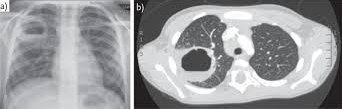

- Mediastinal strukturlara yayılmanı dəqiqləşdirmək üçün KT və endobronxial USM ilk seçimdir (Şəkil 11).

Şəkil 11. Ağciyər xərçənginin diaqnostikası (KT).